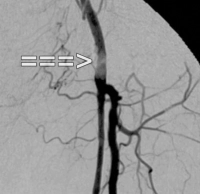

Ejemplo de vídeo: TASC C → reconstrucción abierta

EAP estadio IIb izquierda (distancia de marcha inferior a 100 m). La DSA preoperatoria muestra:

- una estenosis subtotal de la arteria femoral común

- una oclusión de largo recorrido de la arteria femoral superficial en el canal aductor

- oclusiones parciales de las arterias de la pierna inferior